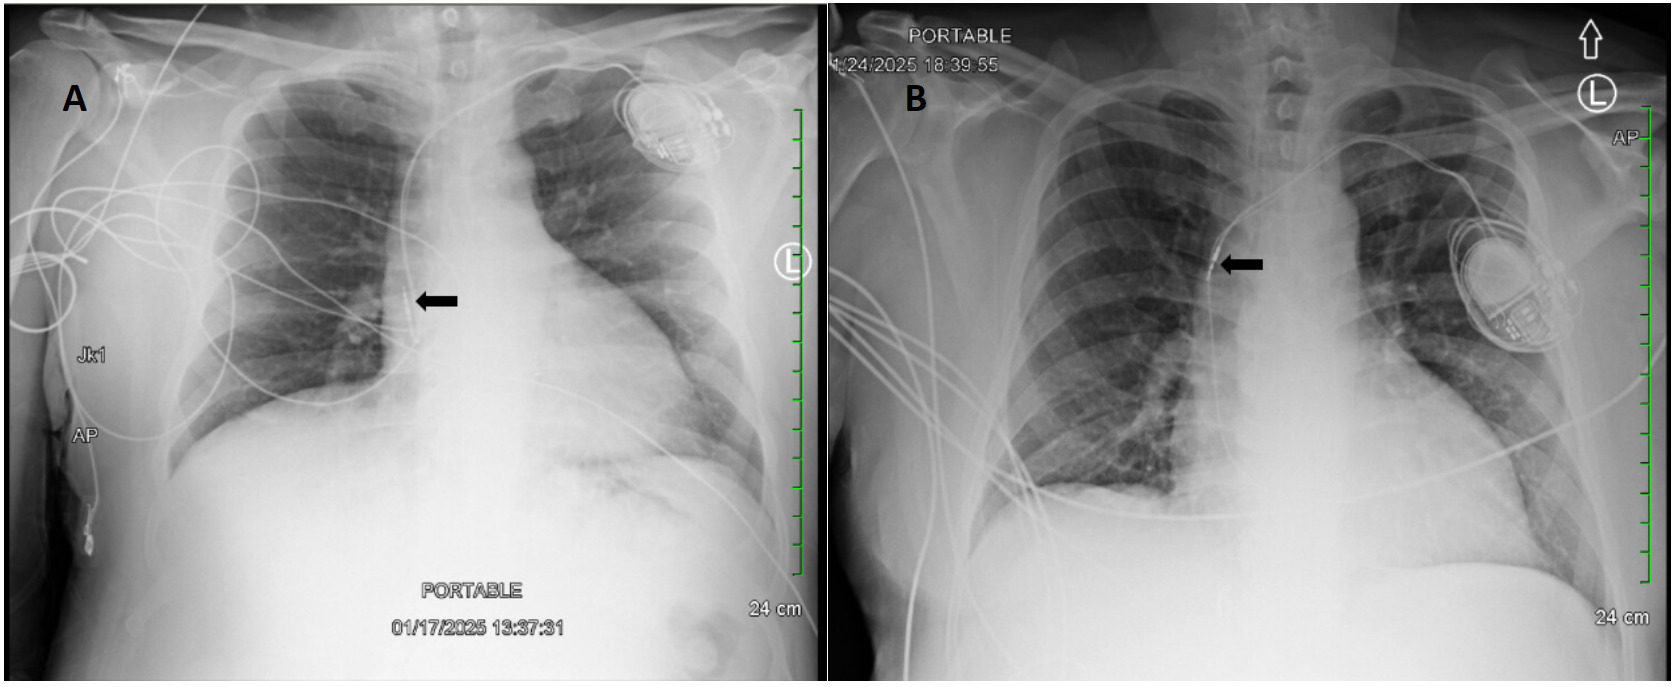

A 62-year-old male with a past medical history notable for left nephrectomy and recent complete heart block status post dual-chamber pacemaker insertion (Figures 1A and 1B) presented with right-sided pectoralis major twitching and persistent singultus. Symptoms began insidiously on post-procedure day five, and after two days of persistent singultus, the patient presented to the hospital. Vital signs were stable, and physical examination revealed ongoing singultus, visible rhythmic contractions of the right chest wall, and no signs of infection at the insertion site or clinical signs of overt heart failure. He denied cough, fever, chest discomfort, shortness of breath, inducible fasciculations, or extremity hypertonia. An electrocardiogram (Figure 1C) demonstrated a paced rhythm consistent with atrioventricular sequential pacing; however, an immediate repeat electrocardiogram (Figure 1D) revealed atrial dissociation with ventricular pacing.

Chest X-rays revealed interval retraction of the atrial lead compared to post-implantation films, with the atrial lead showing migration to the superior vena cava rather than its previous position in the right atrial appendage (Figure 2). Device interrogation confirmed atrial lead dislodgement and subsequent stimulation of the adjacent phrenic nerve. To mitigate symptoms, the pacemaker was reconfigured from initial dual-chamber, rate-adaptive programming (DDDR) to ventricular demand, and rate-adaptive programming (VVIR) to bypass the atrial lead. This change successfully eliminated the diaphragmatic stimulation. He was discharged in stable condition with plans for outpatient atrial lead revision four days later, which was successful.